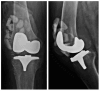

Background: as the demand for total joint arthroplasty continues to grow each year, the healthcare burden is expected to increase due to periprosthetic joint infection (PJI). This review article aims to highlight the significance of biofilms in the pathogenesis of PJI and introduce alternative therapies that prevent bacterial adhesion to implants or enhance their eradication when infection occurs.

Search strategy: we conducted a bibliographic search in PubMed using the following MeSH terms as follows: "no antibiotic treatment of PJI", "bacterial biofilm eradication agents", and "unconventional prevention of PJI", among others. Most important results: after an initial analysis of the literature, we selected the most significant topics on novel PJI treatment methods and prevention strategies. A second PubMed search highlighted the following therapeutic modalities: the application of hydrogels on implant surfaces, the use of phage therapy, lysostaphin and antimicrobial peptides, the implementation of two-stage debridement, irrigation, implant retention and antibiotic therapy (DAIR), the intra-articular antibiotic infusion, and the use of methylene blue for biofilm eradication.

Conclusions: the use of new cement spacers with xylitol, ammonium compounds, or silver nanoparticles is another promising technique to increase the eradication rate in two-stage revision. It is important for professionals to deeply understand the pathogenesis of PJI and the role of biofilms in its development in order to become familiar with these novel techniques that could reduce the burdens on healthcare systems.